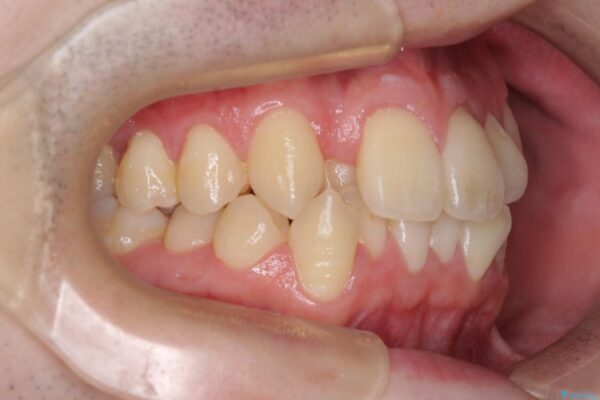

八重歯や奥歯の噛みにくさを気にして来院された患者様です。

前歯のクロスバイトや八重歯の他に、左右最後臼歯のシザーズバイト(鋏状咬合)が認められました。

シザーズバイト改善のために補助装置を使用しながら、ワイヤー装置にて全体の歯列を整えることとしました。

治療前